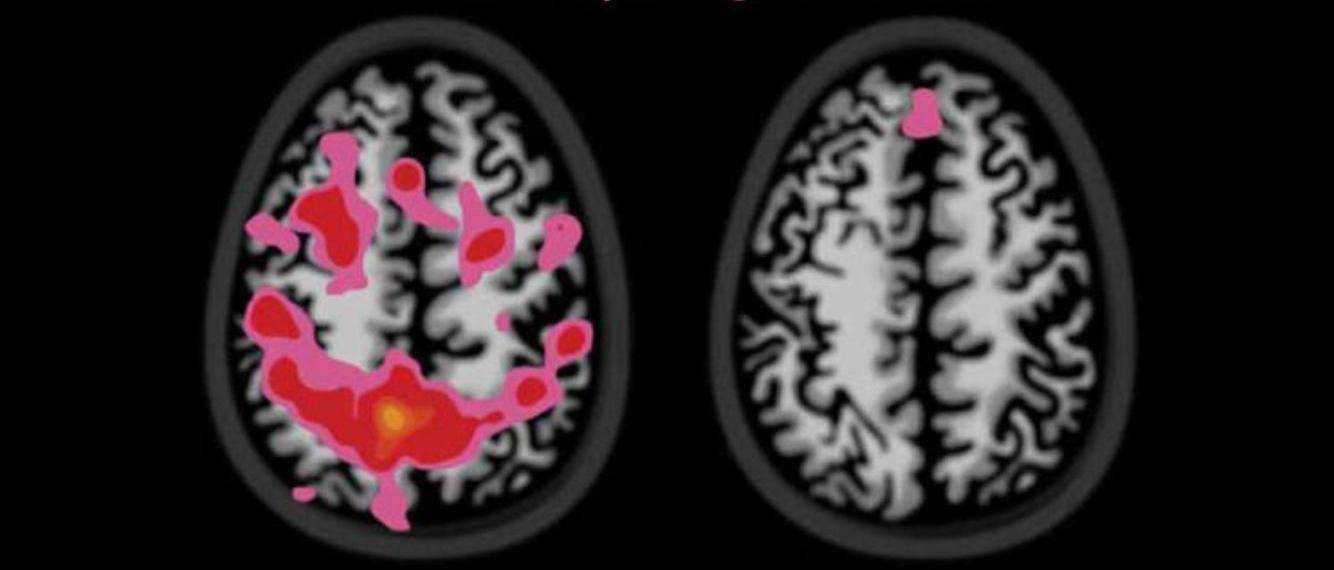

Страдают нервная система и мозг. Под воздействием алкоголя разрушаются нервные клетки и происходят химические реакции в центре мозга. Из-за гибели клеток мозга нарушаются его когнитивные функции.

Страдает нервная система, головной мозг. Под действием алкоголя нейроны разрушаются, в мозговых центрах происходят неправильные химические реакции. Отмирание церебральных клеток приводит к снижению когнитивных функций мозга

Подростки, увлекающиеся выпивкой, менее способны к концентрации внимания, запоминанию новой информации, у них рассеивается внимание. Происходит ухудшение интеллектуальных способностей и моральная деградация. Поражение головного мозга

Поражение головного мозга

Этиловый спирт негативно влияет и на состояние сосудов. В результате снижается кровоснабжение головного мозга. Это приводит к ухудшению работы организма, так как именно мозг контролирует его работу. Развиваются расстройства зрения, слуха, координации.